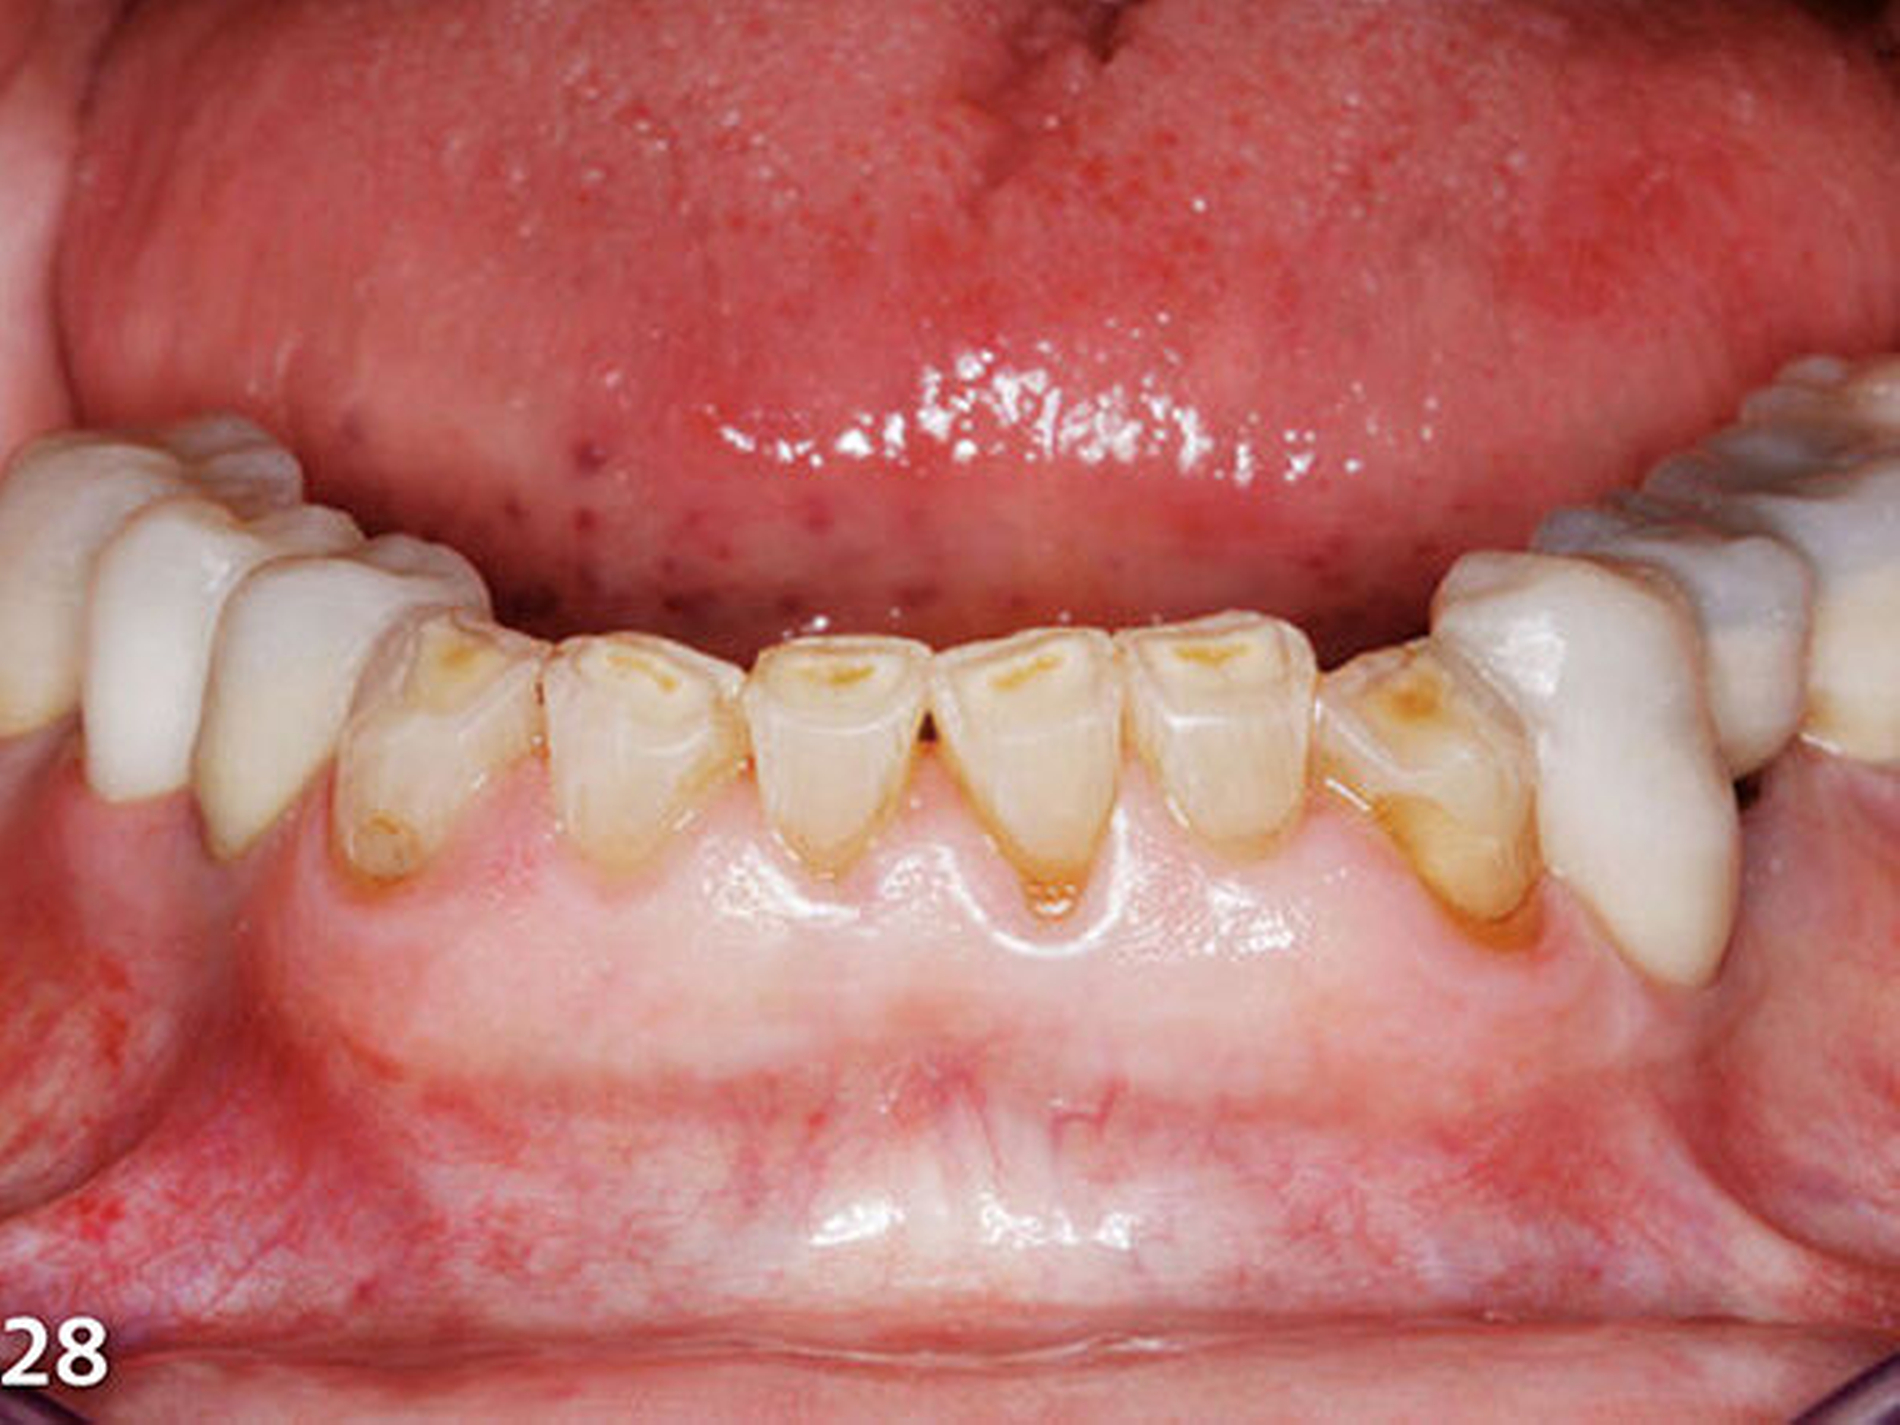

Analog erfolgte der Aufbau der Seitenzahnkauflächen der anderen Kieferhälfte ebenfalls in zwei Schritten (Abb.27). Durch den Aufbau aller Seitenzähne des Unterkiefers ist die temporäre Bisshebung bereits weitgehend abgeschlossen (Abb.28). Mit der dritten Übertragungsschiene (Schiene 3) (Abb.29) wurden die Unterkieferfrontzähne nach Ätzung der Zahnhartsubstanzen mit Phosphorsäure und nachfolgender adhäsiver Vorbehandlung inzisal aufgebaut (Abb.30).